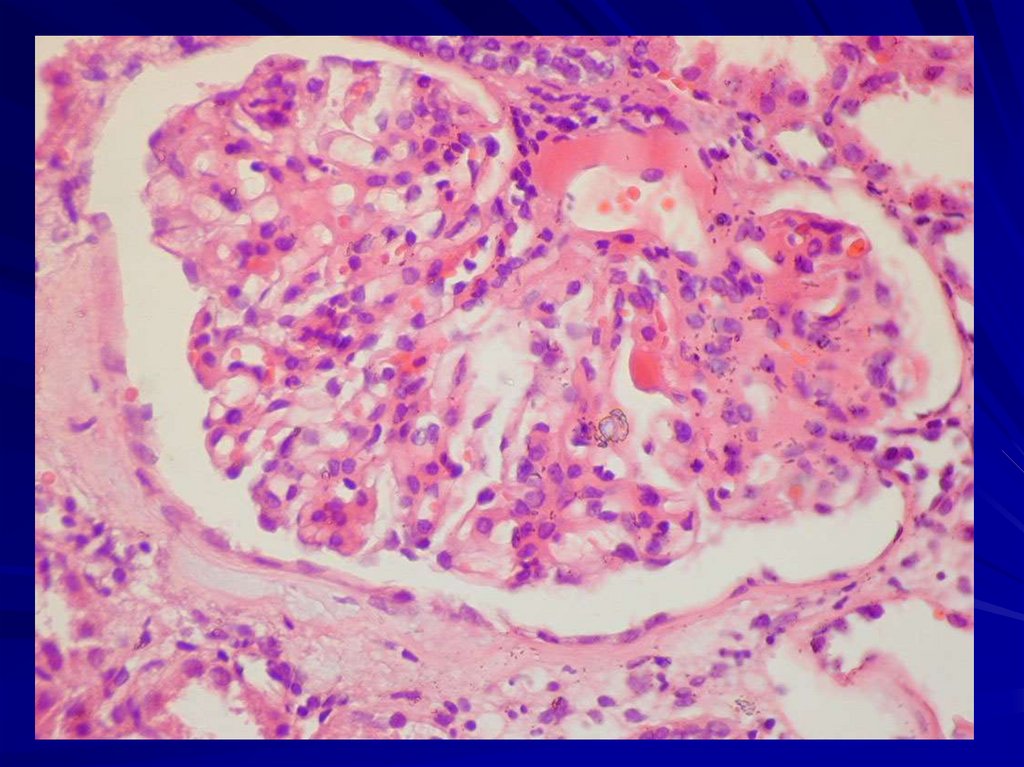

В почках - волчаночный гломерулонефрит.

Микро: "проволочные петли", очаги

фибриноидного некроза, гематоксилиновые

тельца, гиалиновые тромбы.

Морфологически типы гломерулонефрита:

мезангиальный (мезангиопролиферативный,

мезангиокапиллярный)

очаговый пролиферативный,

диффузный пролиферативный,

мембранозная нефропатия.

Исход - сморщивание почек.